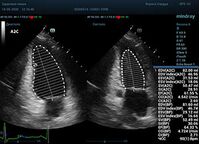

С появлением В режима реализовалась возможность визуализации всех сегментов миокарда из парастернальных и апикальных сечений. Метод Teicholtz в широкой практике сменился методом дисков. Метод дисков, или метод Simpson, позволяет разбить левый желудочек на 20 дисков, с расчетом объема каждого из них. Используя 2 перпендикулярных сечения, апикальные двух и четырех камерное, мы приближаемся к значению реального объема левого желудочка. Исследователь обводит интерфейс эндокард – кровь в фазу диастолы и фазу систолы. Линия простирается от кольца митрального клапана и до кольца митрального клапана, четко разграничивая объем желудочка от предсердия. Для достоверного изменения необходимо использовать ЭКГ канал.

Что могут предложить современные приборы? Приборы нашего времени являются мощными вычислительными машинами, способными обрабатывать полученную информацию даже без помощи человека. Система автоматического вычисления фракции выброса – AUTO EF на приборах серии Resona компании Mindray сделает все за вас. За пару секунд прибор сам отыщет нужную фазу сердечного цикла и произведёт измерение и расчеты, а также покажет график изменения объема в сердечном цикле. От Вас требуется только получить качественное 4С и 2С сечение. Впрочем, прибор всегда оставляет возможность коррекции, если доктор имеет свое мнение на расположение точек планиметрии или момента измерения по ЭКГ каналу.